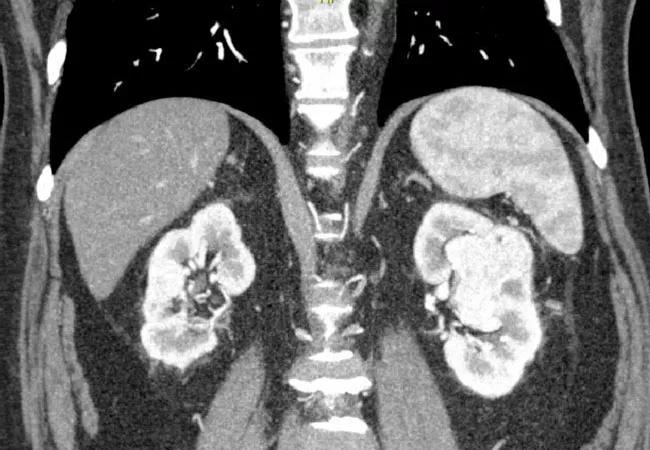

Renal-Cell-Carcinoma_650x450

Advances in immunologic drugs are changing treatment options for patients with metastatic renal cell carcinoma (mRCC). Combinations of monoclonal antibodies against PD-1 or PD-L1 and VEGF inhibitors are showing promising results, compared with single-agent monoclonal antibodies.